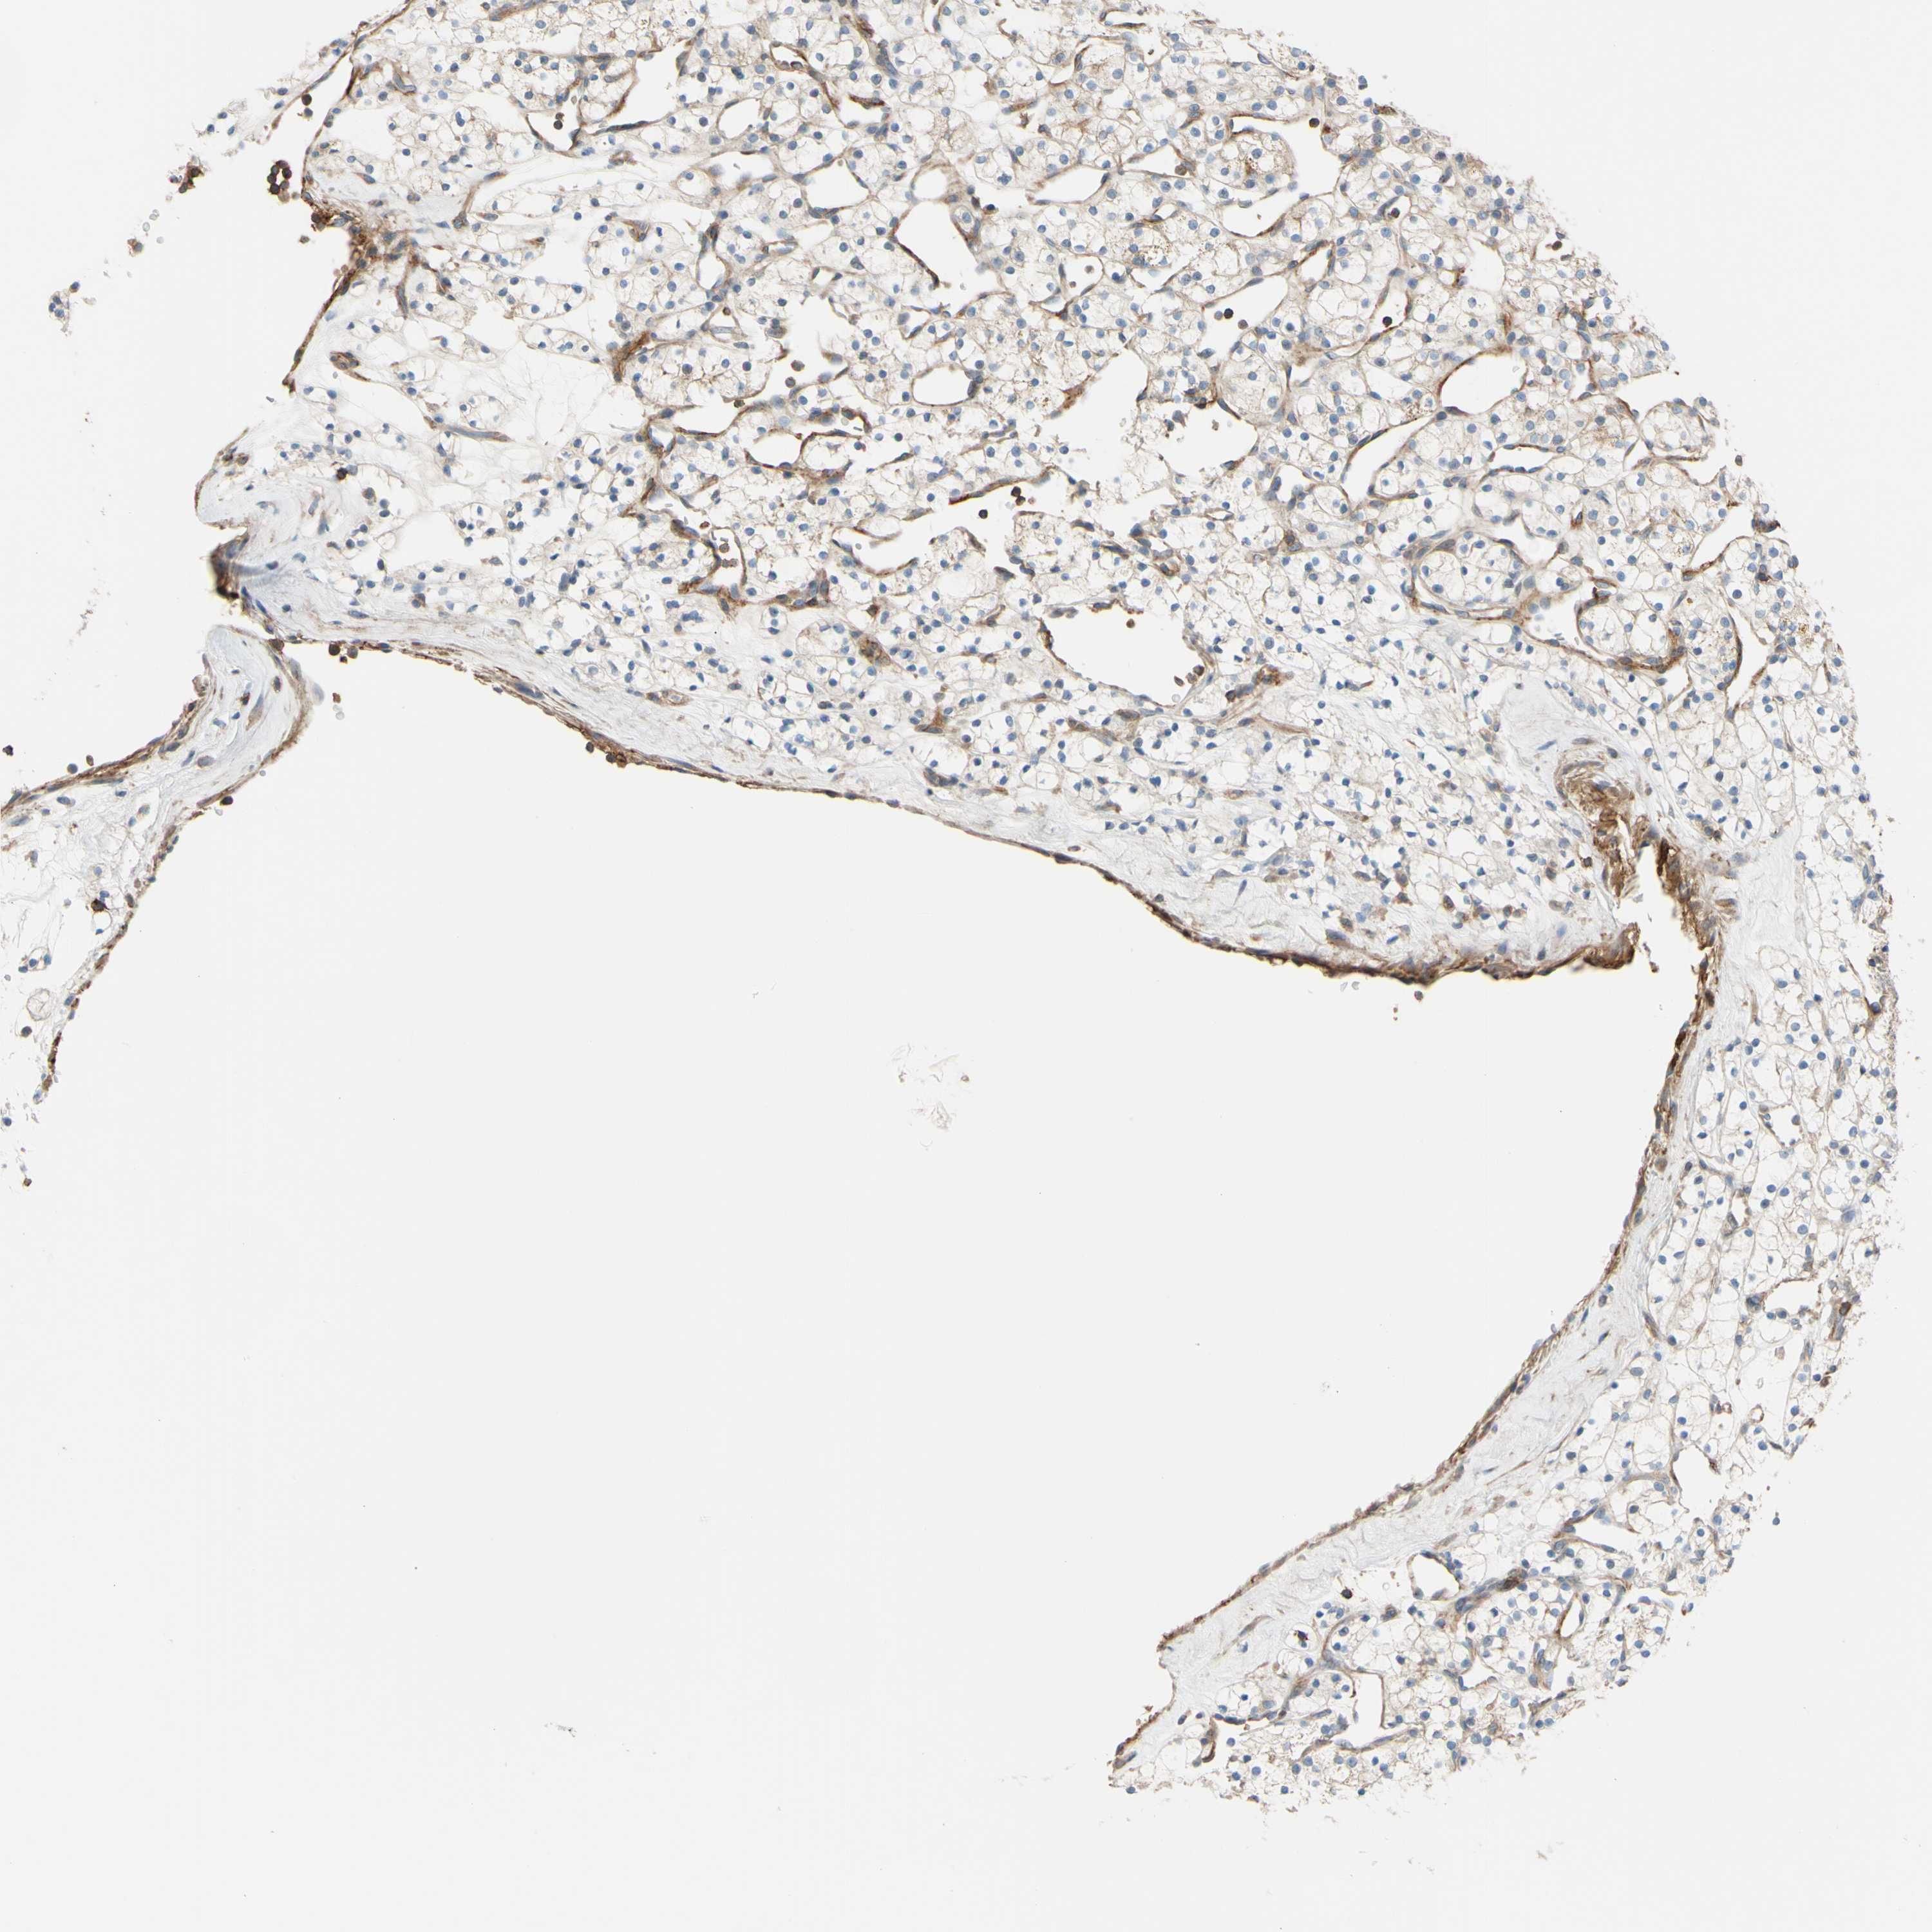

KIDNEY RENAL CLEAR CELL CARCINOMA (VALIDATION) - Interactive survival scatter ploti

The Survival Scatter plot shows the clinical status (i.e. dead or alive) for all individuals in the patient cohort, based on the same data that underlies the corresponding Kaplan-Meier plots. Patients that are alive at last time for follow-up are shown in blue and patients who have died during the study are shown in red.

The x-axis shows the expression levels (FPKM) of the investigated gene in the tumor tissue at the time of diagnosis. The y-axis shows the follow-up time after diagnosis (years). Both axes are complimented with kernel density curves demonstrating the data density over the axes. The top density plot shows the expression levels (FPKM) distribution among dead (red) and alive patients (blue). The right density plot shows the data density of the survived years of dead patients with high and low expression levels respectively, stratified using the cutoff indicated by the vertical dashed line through the Survival Scatter plot. This cutoff is automatically defined based on the FPKM cutoff that minimizes the p-score. The cutoff can be changed by dragging the vertical line or by entering a cutoff value in the square labeled "Current cut-off".

Under the Survival Scatter plot the p-score landscape (black curve; left axis) is shown together with dead median separation (red curve; right axis). Dead median separation is the difference in median mRNA expression between patients who have died with high and low expression, respectively. It is calculated as follows: median FPKM expression of dead patients with high expression - median FPKM expression of dead patients with low expression. This is intended to aid the user in visually exploring custom cutoffs and the associated p-scores and dead median separation.

Individual patient data is displayed and can be filtered by clicking on one or more of the category buttons on the top of the page. Categories describing expression level and patient information include: high, low, alive, dead, female, male and tumor stages. The scale of the x-axis can be toggled between linear and log-scale by clicking on the "x log" button. Mouse-over function shows TCGA ID, patient information and mRNA expression (FPKM) for each patient.

& Survival analysisi

Kaplan-Meier plots summarize results from analysis of correlation between mRNA expression level and patient survival. Patients were divided based on level of expression into one of the two groups "low" (under cut off) or "high" (over cut off). X-axis shows time for survival (years) and y-axis shows the probability of survival, where 1.0 corresponds to 100 percent.

POR is not prognostic in Kidney Renal Clear Cell Carcinoma (validation)

Best expression cut offi

Based on the FPKM value of each gene, patients were classified into two groups and association between prognosis (survival) and gene expression (FPKM) was examined. The best expression cut-off refers the FPKM value that yields maximal difference with regard to survival between the two groups at the lowest log-rank P-value. Best expression cut-off was selected based on survival analysis .

When clicking on this number, the vertical dashed line indicating cut-off, the interactive survival plot, and the Kaplan-Meier curve will be adjusted to show results based on the best expression cut-off.

: 61.46

TCGA RNA samplesi

RNA-seq data is reported as average FPKM (number Fragments Per Kilobase of exon per Million reads), generated by the The Cancer Genome Atlas (TCGA) .

Normal distribution across the dataset is visualized with box plots, shown as median and 25th and 75th percentiles. Points are displayed as outliers if they are above or below 1.5 times the interquartile range. FPKM values of the individual samples are presented next to the box plot.

Average pTPM 54.3

Number of samples 100